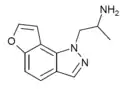

2-desethyl-YM-348 [32] | (2S)-1-(1H-furo[2,3-g]indazol-1-yl)propan-2-amine | 748116-94-1 |

|